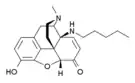

Several semi-synthetic opioids were developed in Germany in the 1910s. The first, oxymorphone, was synthesized from thebaine, an opioid alkaloid in opium poppies, in 1914.[228] Next, Martin Freund and Edmund Speyer developed oxycodone, also from thebaine, at the University of Frankfurt in 1916.[229] In 1920, hydrocodone was prepared by Carl Mannich and Helene Löwenheim, deriving it from codeine. In 1924, hydromorphone was synthesized by adding hydrogen to morphine. Etorphine was synthesized in 1960, from the oripavine in opium poppy straw. Buprenorphine was discovered in 1972.[228]

Opium alkaloids and derivatives

Phenanthrenes naturally occurring in (opium):

Semi-synthetic alkaloid derivatives

- Buprenorphine

- Etorphine

- Hydrocodone

- Hydromorphone

- Oxycodone (sold as OxyContin)

- Oxymorphone